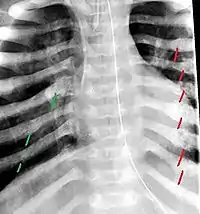

The material factual allegations of the amended complaint are as follows. Plaintiff was born on May 14, 1970. On repeated occasions during the first year of her life she was severely beaten by her mother and the latter's common law husband, one Reyes. On April 26, 1971, when the plaintiff was eleven months old, her mother took her to the San Jose Hospital for examination, diagnosis, and treatment. The attending physician was defendant Dr. Flood, acting on his own behalf and as agent of the defendant San Jose Hospital. At the time, the plaintiff was suffering from a comminuted spiral fracture of the right tibia and fibula, which gave the appearance of having been caused by a twisting force. Plaintiff's mother had no explanation for this injury. Plaintiff had bruises over her entire body. In addition, she had a non-depressed linear skull fracture which was then in the process of healing. Plaintiff demonstrated fear and apprehension when approached. Inasmuch as all plaintiff's injuries gave the appearance of having been intentionally inflicted by other persons, she exhibited the medical condition known as the battered child syndrome.

It is alleged that proper diagnosis of plaintiff's condition would have included taking X-rays of her entire skeletal structure, and that such procedure would have revealed the fracture of her skull. Defendants negligently failed to take such X-rays, and thereby negligently failed to diagnose her true condition. It is further alleged that proper medical treatment of plaintiff's battered child syndrome would have included reporting her injuries to local law enforcement authorities or juvenile probation department. Such a report would have resulted in an investigation by the concerned agencies, followed by a placement of plaintiff in protective custody until her safety was assured. Defendants negligently failed to make such report.

For example, the leading article by Kempe et al., op. cit., supra,[11] states that "A physician needs to have a high initial level of suspicion of the diagnosis of the battered-child syndrome in instances of subdural hematoma, multiple unexplained fractures at different stages of healing, failure to thrive, when soft tissue swelling or skin bruising are present, or in any other situation where the degree and type of injury is at variance with the history given regarding its occurrence . . . ." (Id., at p. 20.) Of the different types of fractures exhibited, an arm or leg fracture caused by a twisting force is particularly significant because "The extremities are the 'handles' for rough handling" of the child by adults. (Id., at p. 22.) The article also contains numerous recommendations to conduct a "radiologic examination of the entire skeleton" for the purpose of confirming the diagnosis, explaining that "To the informed physician, the bones tell a story the child is too young or too frightened to tell." (Id., at p. 18.) Finally, on the subject of management of the case it is repeatedly emphasized that the physician "should report possible willful trauma to the police department or any special children's protective service that operates in his community" (id., at p. 23) in order to forestall further injury to the child: "All too often, despite the apparent cooperativeness of the parents and their apparent desire to have the child with them, the child returns to his home only to be assaulted again and suffer permanent brain damage or death." (Id., at p. 24.)